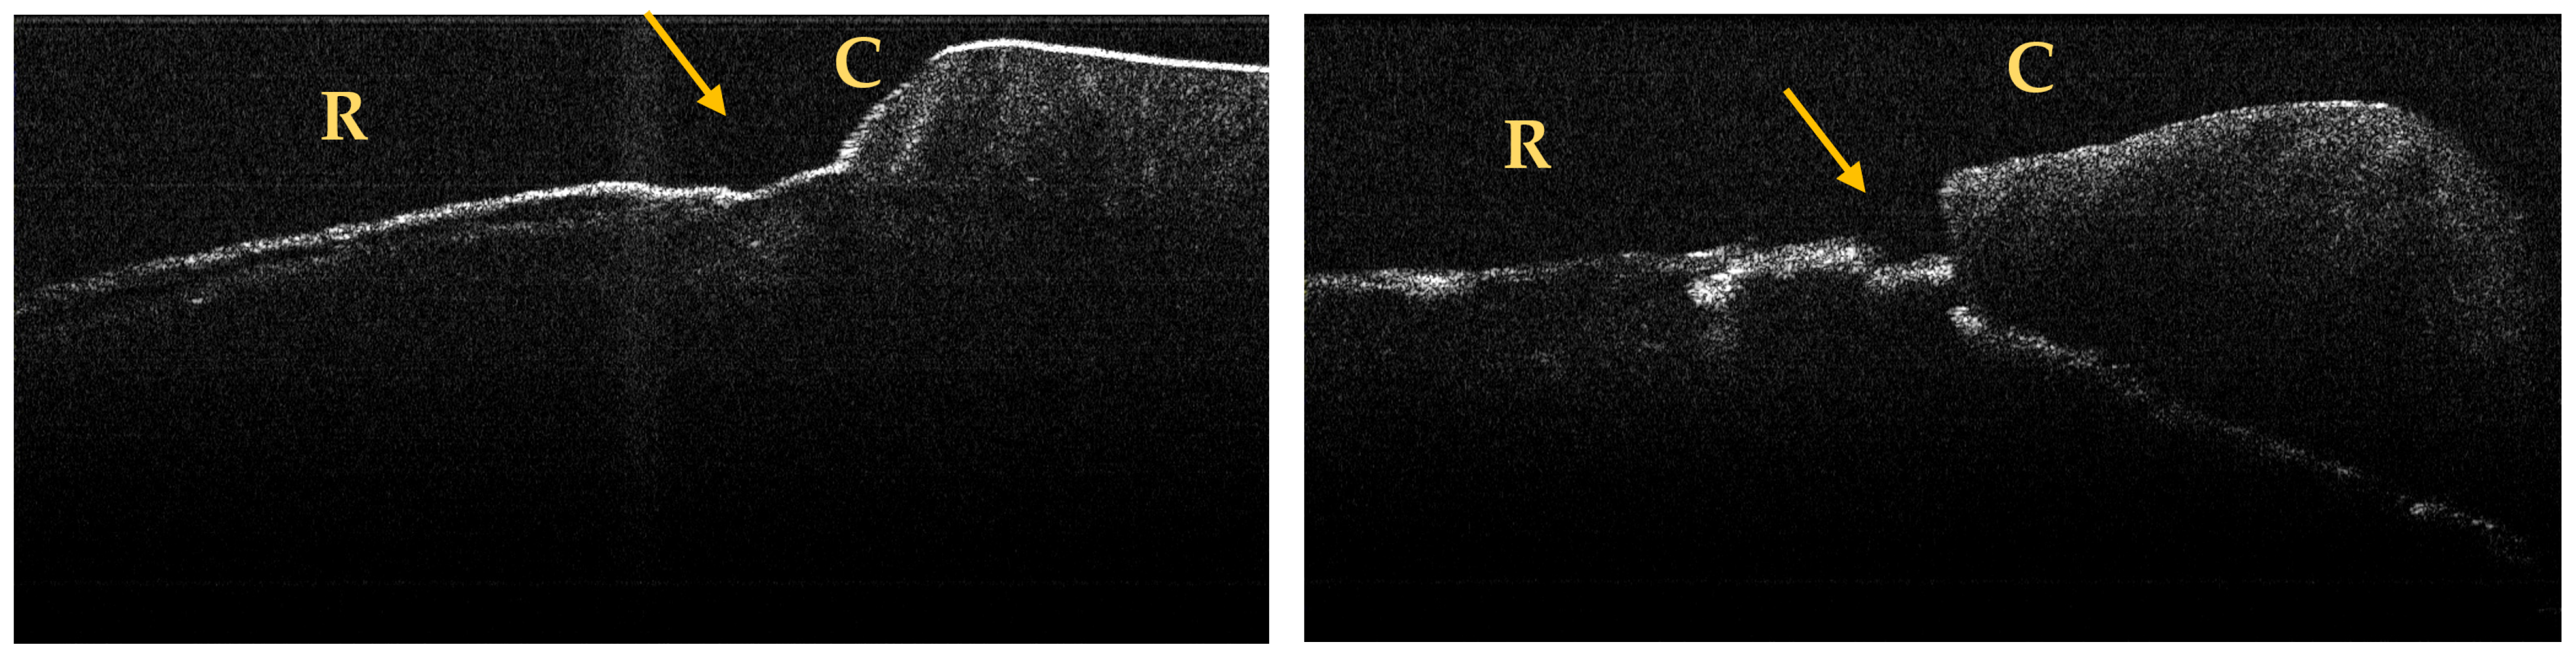

A maximum of 512 OCT images was taken for each dental surface examined. Figure 3, Figure 4 and Figure 5 present specific OCT images of teeth with macroscopically identified NCCLs, but also specific OCT images of teeth in which the NCCLs were not visible macroscopically. In each figure depicting the OCT images obtained, the position of the dental crown is marked with the letter C, the position of the root is marked with the letter R, and the arrow indicates the NCCL.

Figure 4.

OCT images of a saucer-shaped NCCL, indicated by the arrows.